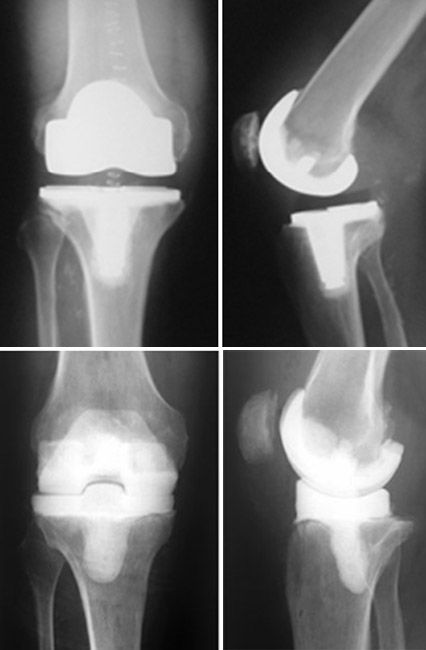

Knee replacement surgery can eliminate the pain from arthritis and improve your quality of life. So preventive treatment is advised if the dental procedure involves high levels of bacteria. When my knee was replaced with an artificial joint, the surgeon said i should always take antibiotics before any dental procedure. Prosthetic joint infection (pji) of total hip (tha) or total knee arthroplasty (tka) after dental procedures is uncommon, and antibiotic . You should get preventive antibiotics before dental procedures if:.